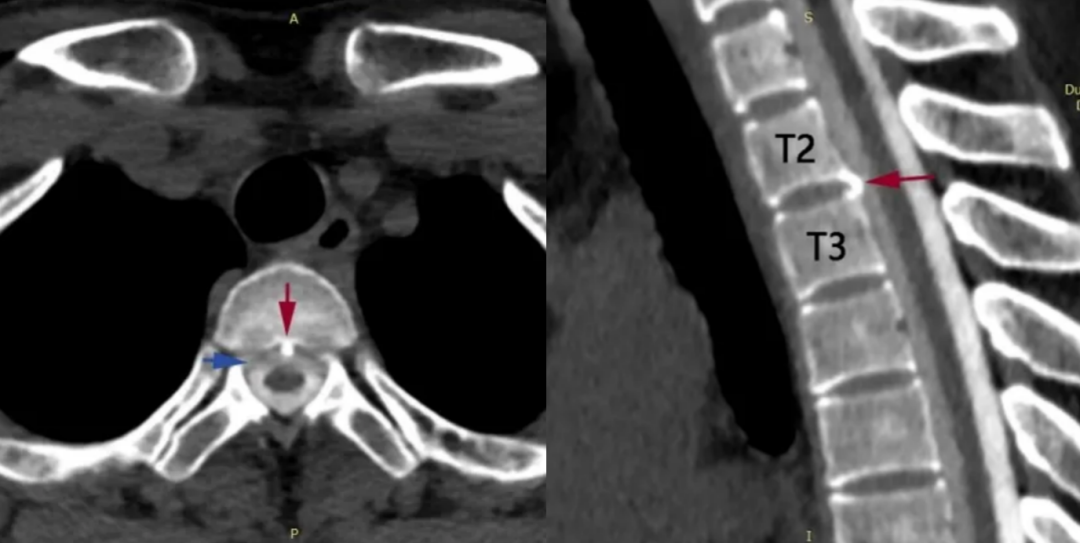

第2、3胸椎之间有“骨刺”形成(红箭头)

刺破硬脊髓膜,造成脑脊液外漏(蓝箭头)